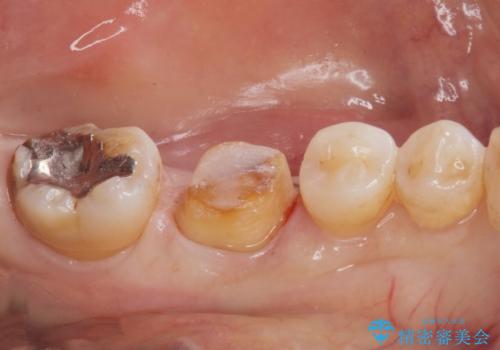

- 奥歯の銀の詰め物が取れたとの事で来院。

詰め物の下に虫歯ができて銀歯が取れてしまった事が予想されます。

白い詰め物でやり直しをしても歯質が薄くなり割れてしまうリスクがあるために、

割れるリスクの少ないジルコニアクラウンにて治療しました。